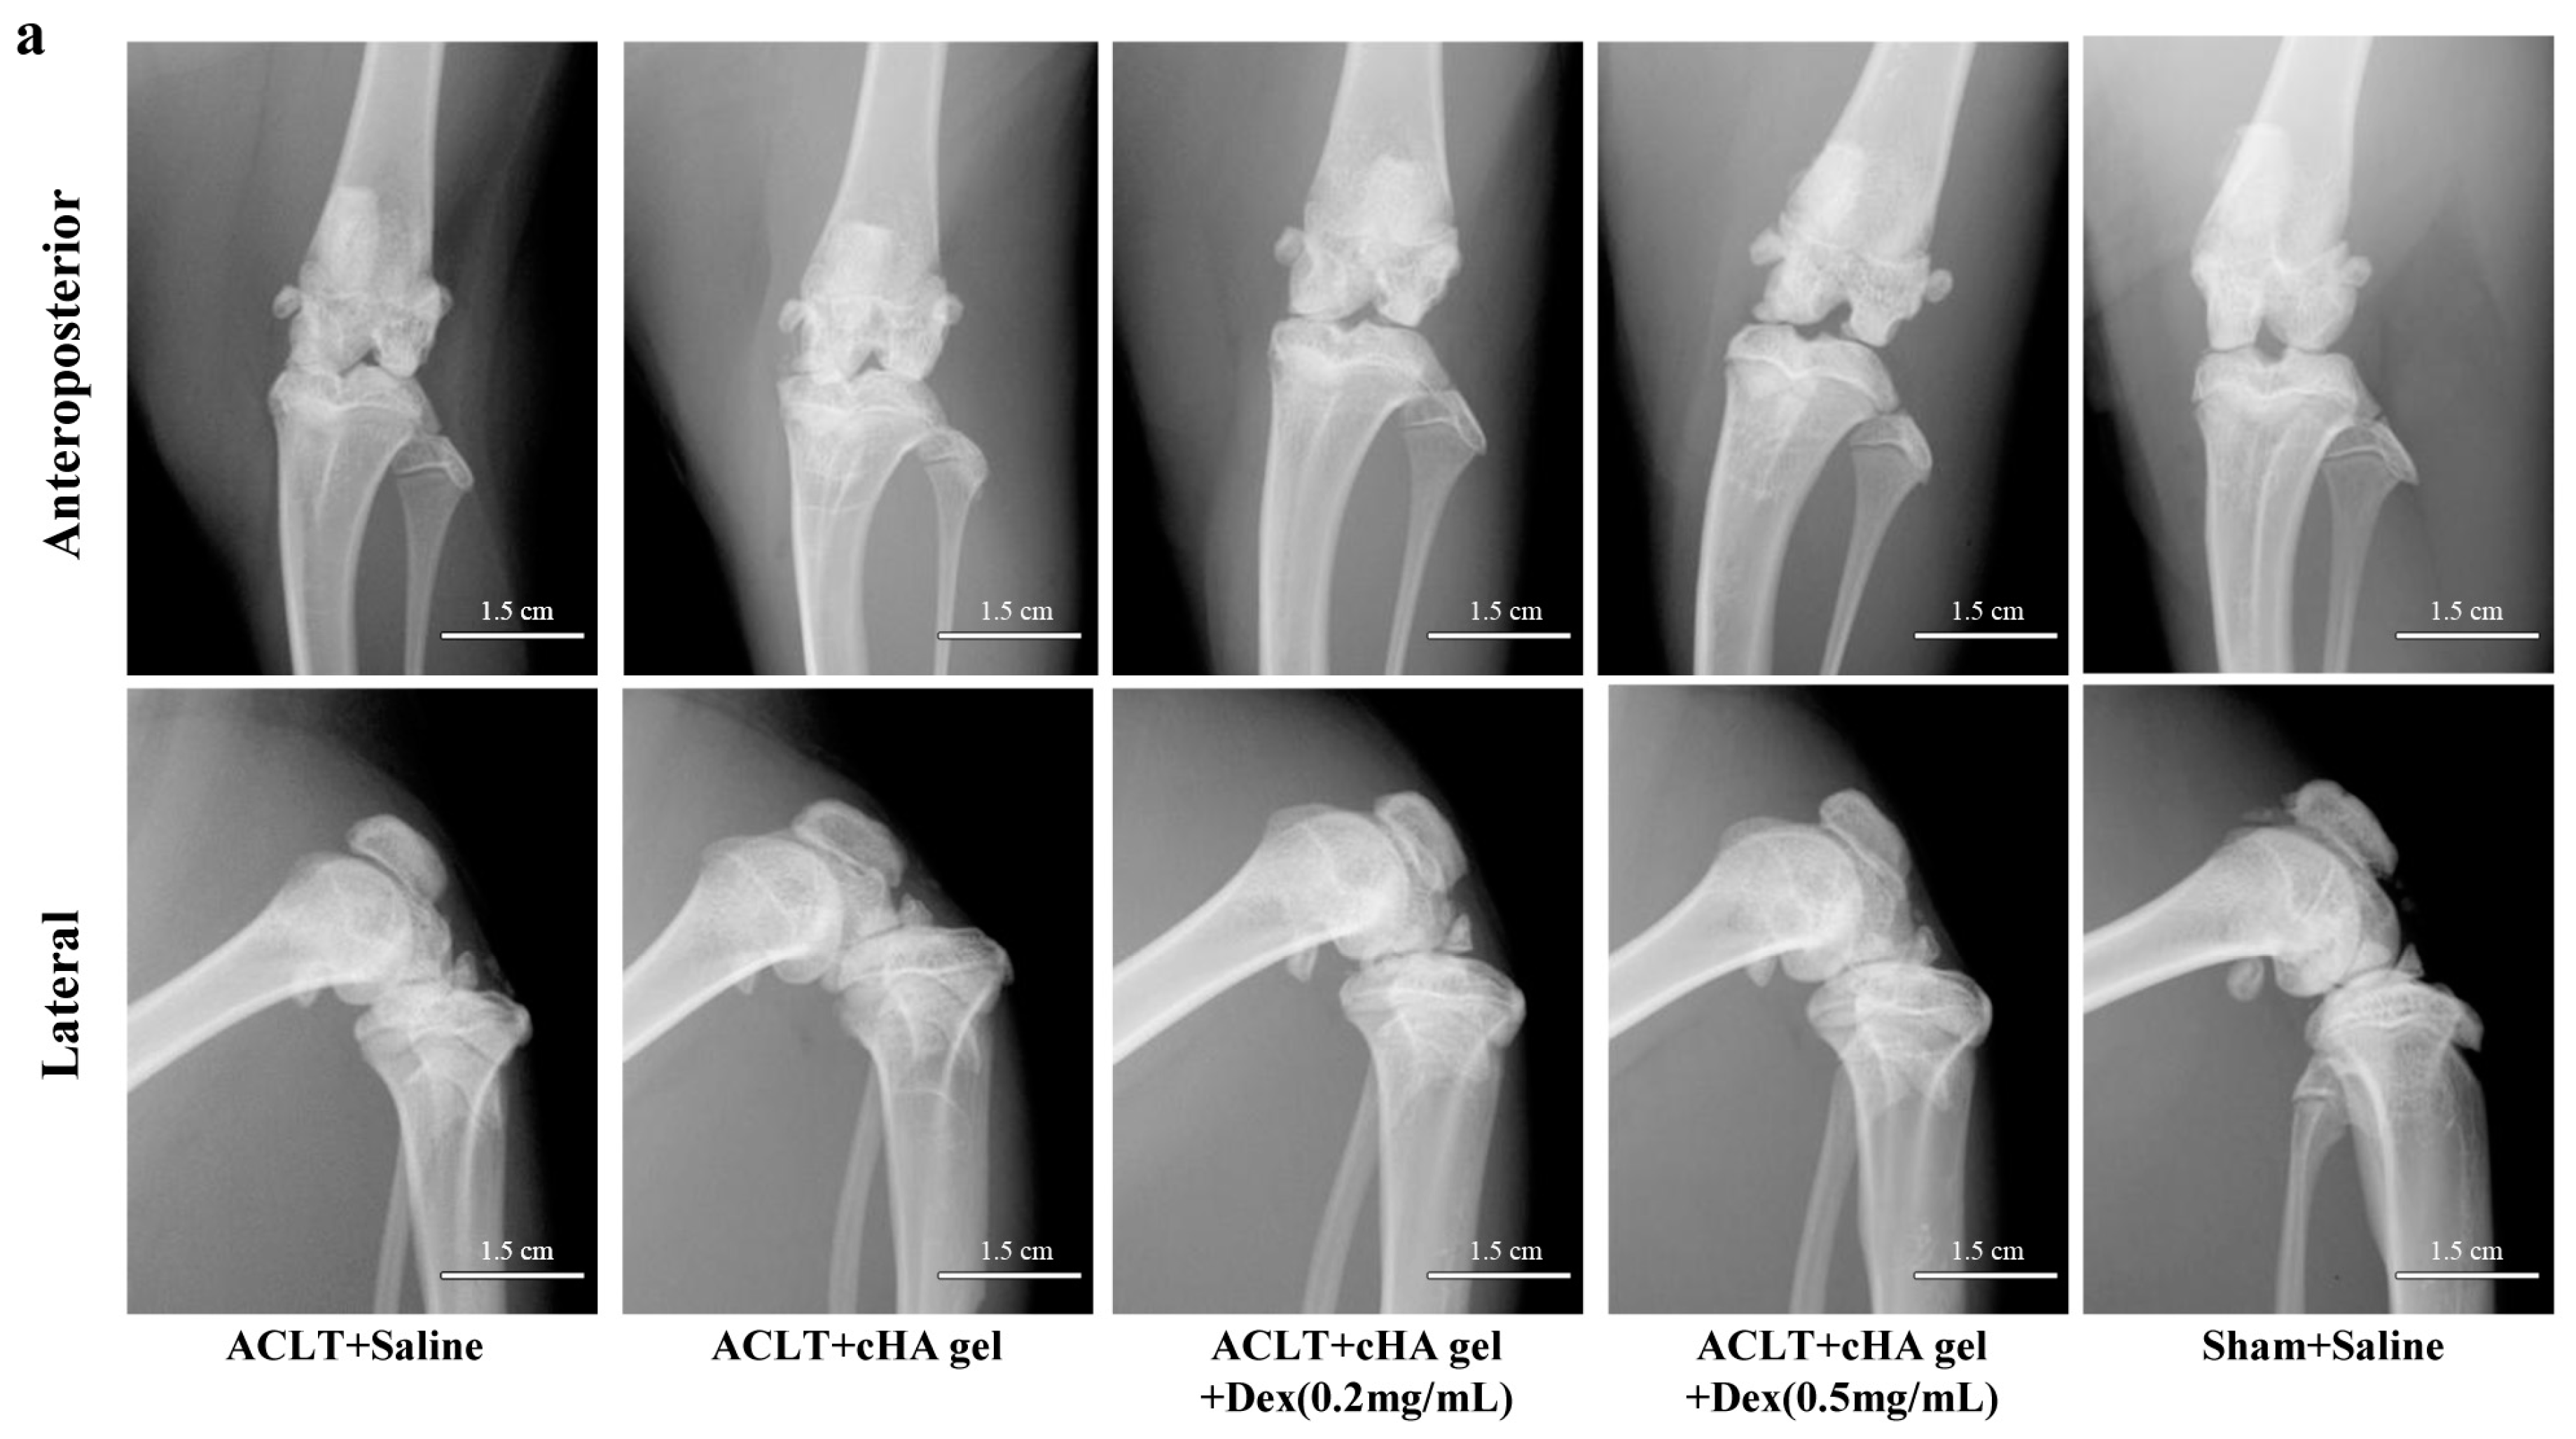

2.2. Intra-Articular cHA-Dex Hydrogel Injection Attenuated Osteoarthritis (OA) Macroscopically

4.3. Radiography